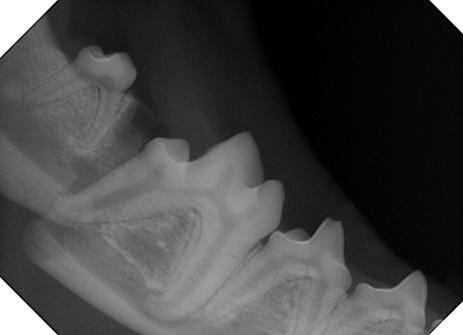

Figure 1. Radiograph of a dog’s mandible after it has been fractured during an altercation with another dog